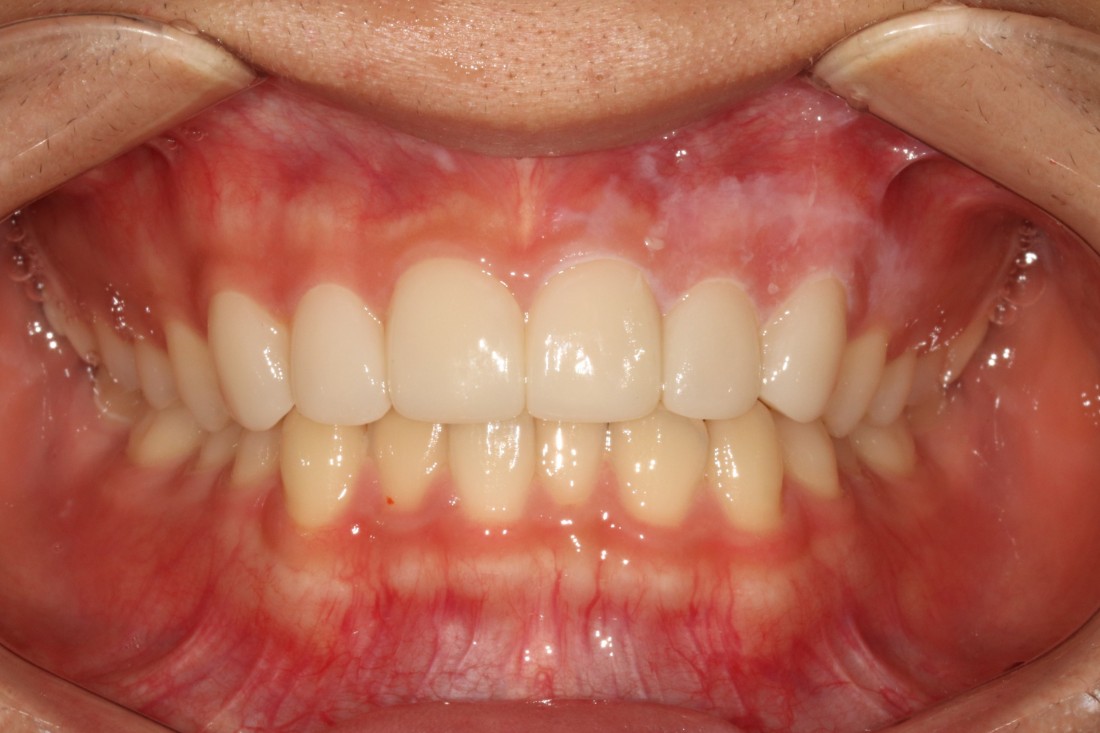

광주 라미네이트 치과는

서울 강남에서 라미네이트 진료만을

10년 넘게 담당해오고 계신

전문의 고석호 대표원장님께서

직접 상담부터 디자인, 시술 및 관리까지

모든 과정을 1:1 케어로 진료하기 때문에

서울 강남까지 가지 않으셔도

광주 라미네이트 치과에서

서울 의료진 기술과 실력 그대로

최상급 라미네이트 진료를 받으실 수 있습니다.

오랜 시간 연구 끝에 개발한

무삭제(최소삭제) 라미네이트

새로네이트 진료를 통하여

치아 삭제량을 최소화하였기 때문에

치아 시림에 대한 우려를 줄였습니다.